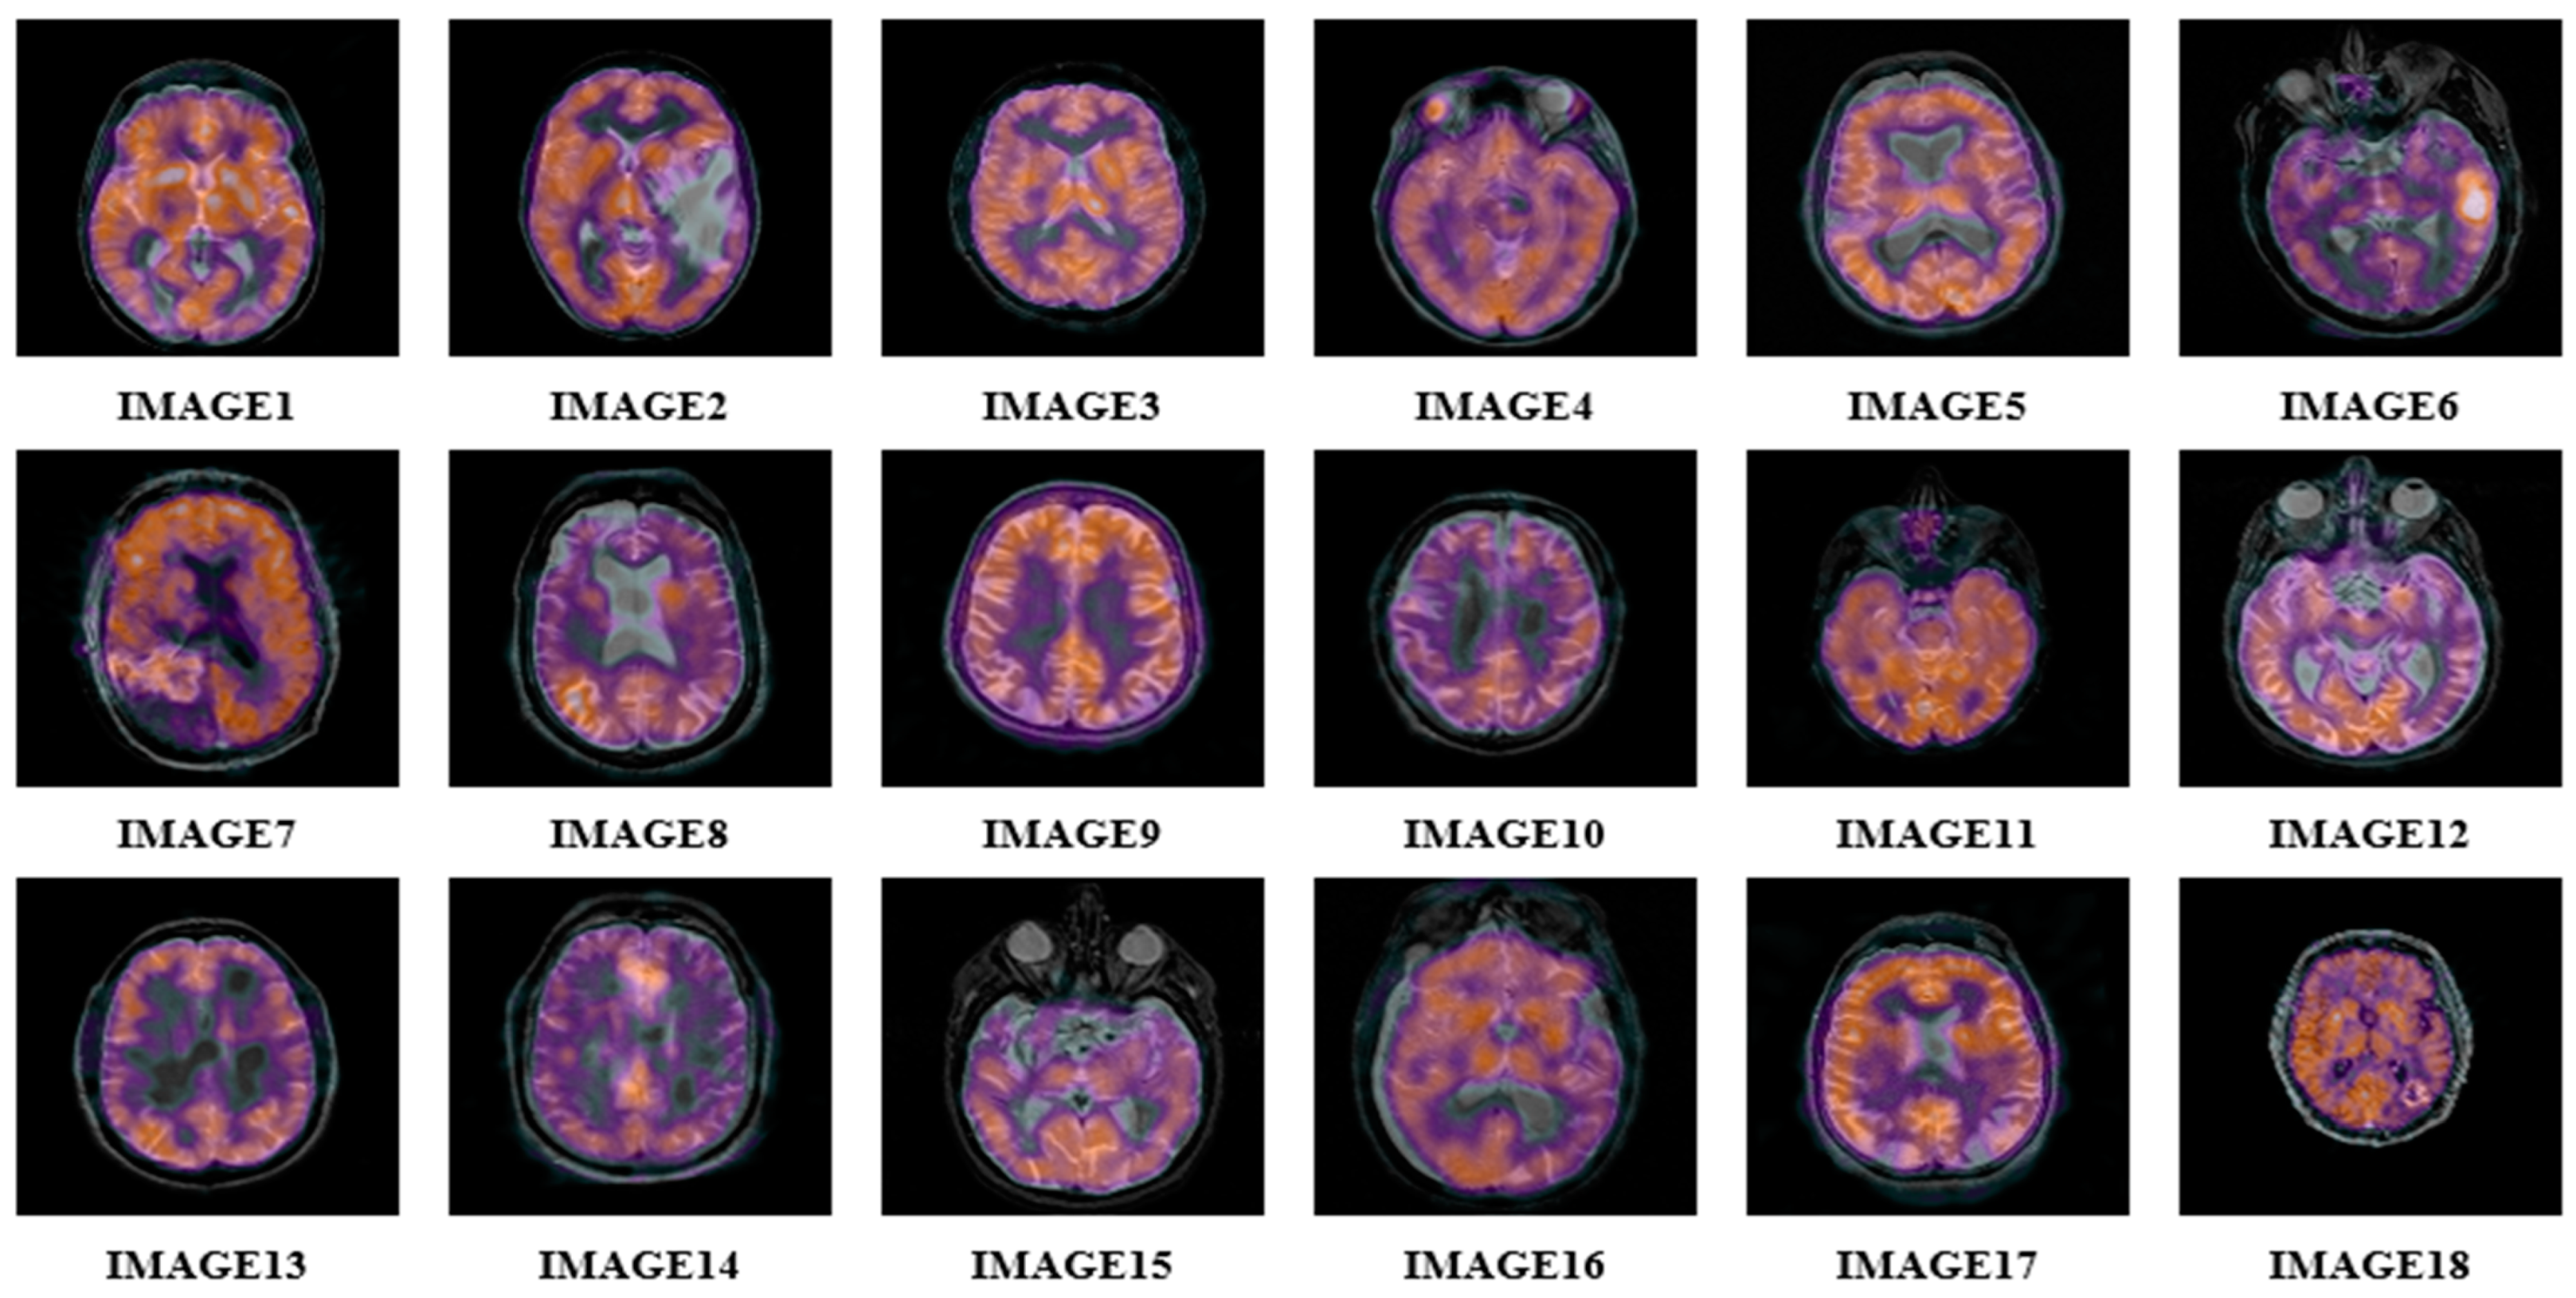

- Johnson, K.A.; Becker, J.A. The Whole Brain Atlas. Available online: http://www.med.harvard.edu/AANLIB/home.html (accessed on 19 April 2022).